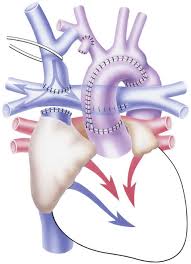

Value added benefits of the B.T. Shunt:

Value added benefits of the Double Valve Replacement and CABG:

Value added benefits of the Total Correction with Single Valve Repair or Replacement: